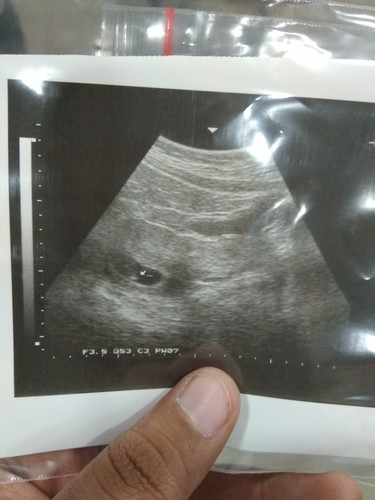

Ini hasil USG transvaginal tadi siang.. kalo dihitung dr hpht harusnya 8w3d Tapi di USG 4w5d. Belum kelihatan janinnya.. dan 2 Minggu kedepan kalo ga ada janinnya suruh kuretes ๐ญ doain ya bunda2 semoga ini rejeki aku dan suami ..

Itu udah kelihatan embrionya belum sih bun... ?? Penasaran Soalnya kmren ak usg masih kantong aja.. sama dokternya di kasih tau ini ukuran kantong sesuai sama usia kehamilannya gitu.

Pas USG ga di tanyakan ke dokternya bund? bukannya biasanya dokternya menjelaskan dokternnya blg apa bund? klo saya usg 8 week bulatannya lbh besar, tp jnainnya blom kelihatan

Baca lagiBrp cm itu?ini pnyku 7w2d. Semoga sehat ya..ga perlu dipikirin normal atau ga gedenya..masih keciiilll banget

ini usg aku 8 week 3 hari bund.. tp temen aku jg ada koo seperti bunda, tungguin aja bund. 3 bulan baru usg lg